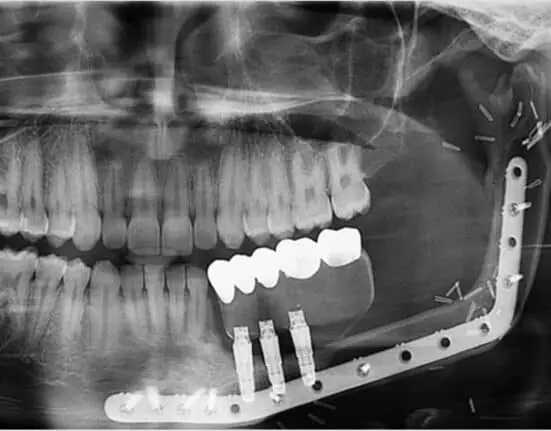

During the study, no tumors recurred after the procedure using microvascular free fibula grafts, which fill in jawbone with fibula leg bone. The grafts have their own blood supply through small blood vessels moved with the transplanted bone.

Also, no complications resulted from eight dental implants, which replaced missing teeth. Three minor complications, two incision reopenings and an infection, occurred within 30 days after the procedure at the site where the fibula was removed.

The protocol used digital planning to prepare for tumor location, extent, and removal, the graft, and the reconstruction plate, reducing surgical time and helping determine exact insertion of the fibula for dental implant placement, the researchers said.